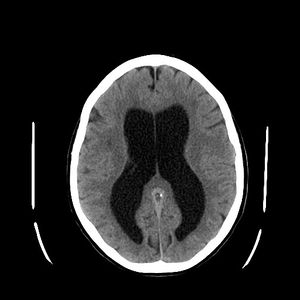

نزيف تلقائي داخل نسيج الدماغ وداخل البطينات لمريض يعاني من استسقاء الرأس كما يظهر في الصورة المقطعية.

استسقاء الرأس كما يظهر في الأشعة المقطعية للدماغ، يشير اللون الأسود في منتصف نسيج المخ إلى تضخم حجم بطينات المخ حيث أنه في الطبيعي يكون هذا الحيز أصغر حجمًا.